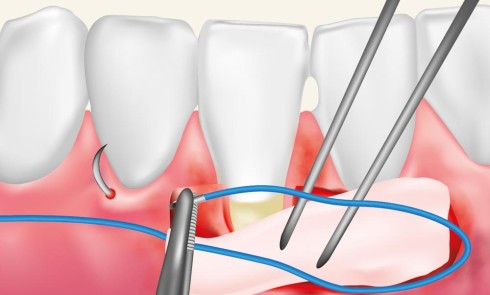

Article réservé à nos abonnés La greffe épithélio-conjonctive : incisions et sutures pas à pas

Après une désinfection exobuccale et endobuccale à la povidone iodée, une anesthésie traçante para-apicale 1/100 000 d’articaïne est réalisée au niveau...